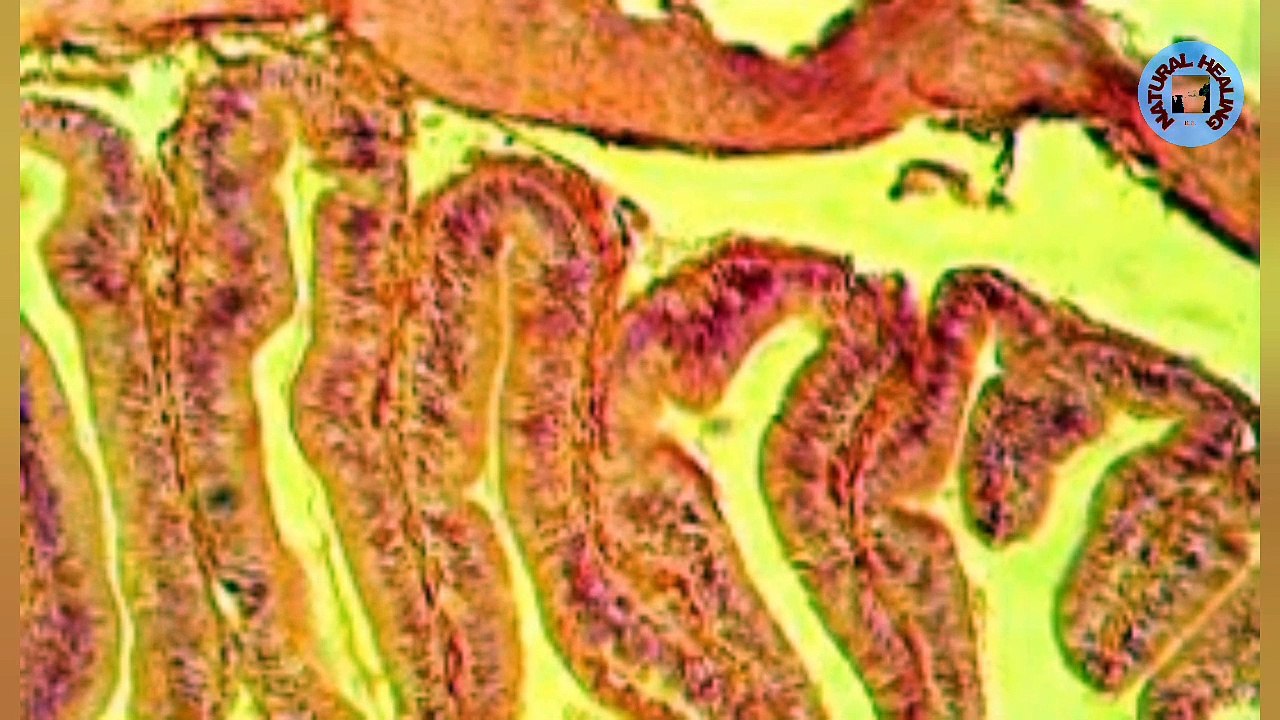

Hello everyone!!<br /><br />This video is about some interesting and amazing facts about human body but rarely known...<br />So sit back and enjoy the video while gaining new knowledge...<br /><br />If you find the video informative, do LIKE and SHARE it to your loved ones and FOLLOW Facts In Reels for more such videos...